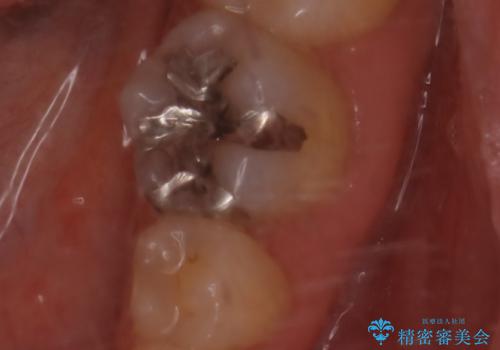

- 大きく口を開けると目立つ銀歯のやり替えをご希望された患者様です。適合のよいセラミックインレーで補綴することで、将来的な虫歯発生のリスクを最小限に抑え、機能面でも安心して使っていただけるようにしました